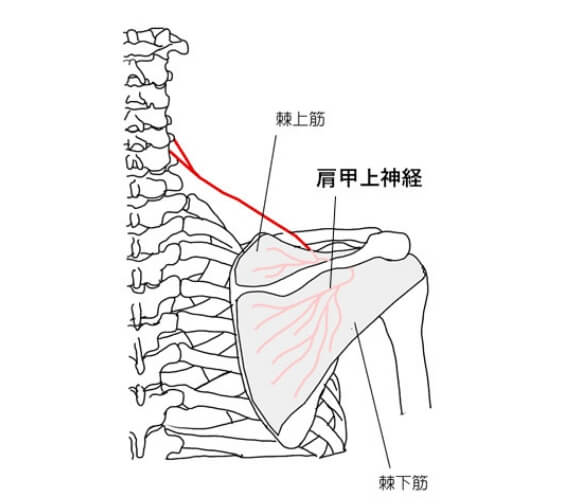

肩を使った時に痛みます。肩の不安定感・脱力感をともなうこともあります。また、投球時のフォロースルーの際に、肩が抜けるように感じることもあります。5.肩甲上神経損傷(けんこうじょうしんけいそんしょう)

棘下筋を支配している肩甲上神経が、投球のフォロースルーのような動作のときに引っ張られたり、圧迫されたりして損傷をおこしたものです。野球の投球の他、テニスのサーブやスマッシュ、バレーボールのスパイクなどでも起こります。

肩の痛みが肩の後ろ外側に放散します。肩甲骨の山が目立つようになります。肩全体に疲労感があります。